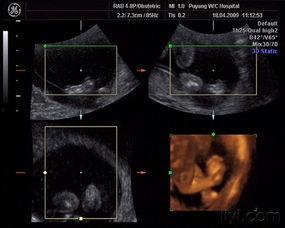

图片二:宝宝在肚子里的小动作

这张图片记录了宝宝在妈妈肚子里的一个可爱瞬间。你可以看到,宝宝的小手和小脚在妈妈的肚子里轻轻摆动,仿佛在向世界打招呼。这个瞬间,是不是让你感受到了母爱的伟大和生命的神奇?